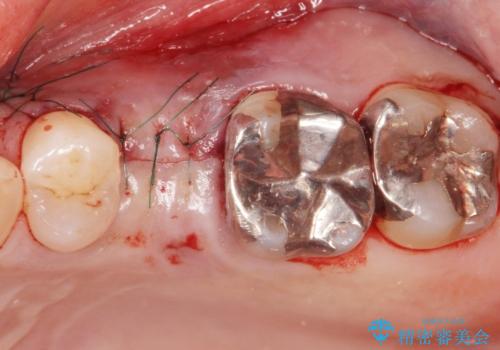

歯茎が腫れる インプラントでの治療

- 左上5/インプラント:242,000円 骨増生:55,000円 カスタムアバットメント:110,000円 インプラント用仮歯:22,000円 ジルコニアクラウン:121,000円 合計550,000円費用は治療当時の料金となります